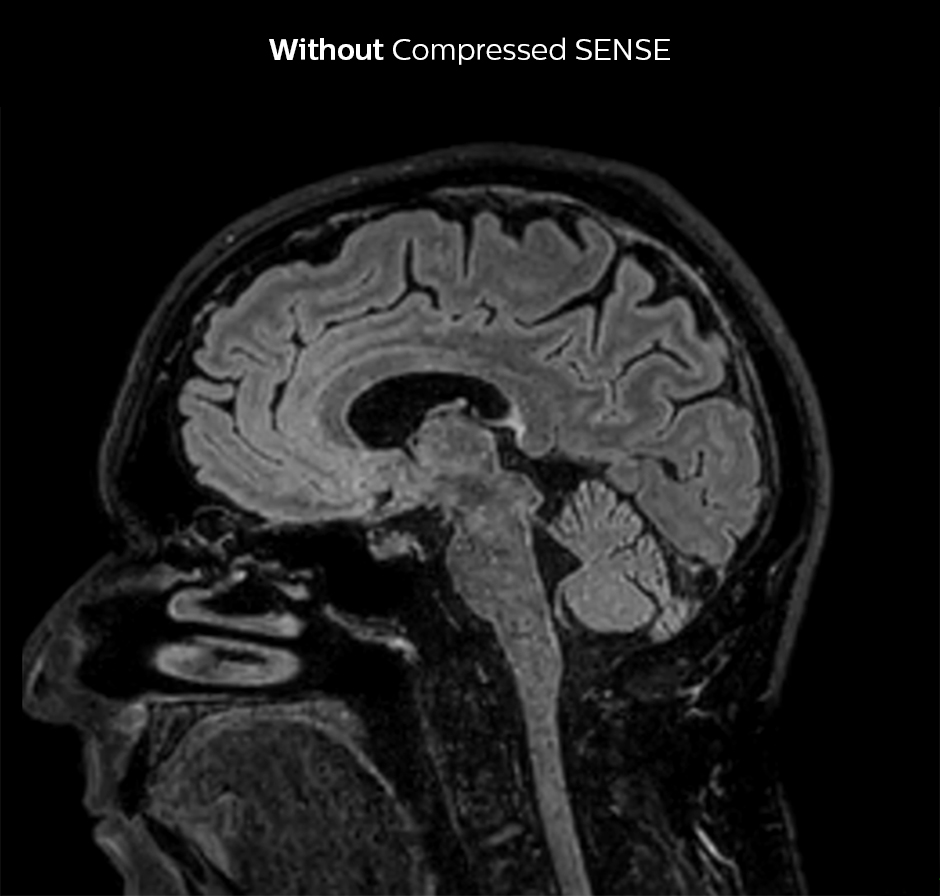

Dr. Sartoretti weet nog goed hoe ze meteen tijdens de eerste scans onder de indruk was van Compressed SENSE. “Onze eerste sequentie met Compressed SENSE was een 3D FLAIR in de hersenen op de Ingenia 1.5T, waarbij we een Compressed SENSE-factor van 8.2 toepasten. Daarna hebben we een 3D TSE mDIXON post-contrastsequentie met een CS-factor van 7 uitgetest. In beide gevallen was de kwaliteit bijzonder goed.“

3D FLAIR, scantijd 5:02 min, voxelgrootte 1,1x1,1x1,1 mm, Ingenia 1.5T.

3D FLAIR, scantijd 3:36 min, voxelgrootte 1,1x1,1x1,1 mm, Ingenia 1.5T.

Compressed SENSE verkort de scantijd met 28%, mét behoud van dezelfde ruimtelijke resolutie.